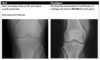

Colles vs Smith fracture

Colles fracture ## Footnote Typically FOOSH forwards Extra-articular radial # with dorsal (posterior / back of hand) angulation and displacement

Smith Fracture ## Footnote Typically FOOSH back of hand Extra-articular radial # with volar (anterior / palmar) angulation and displacement